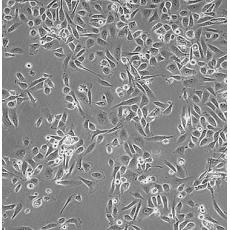

PC-3M

產(chǎn)品名稱 PC-3M

中文名稱 人前列腺癌細(xì)胞

組織來源 前列腺癌;骨髓轉(zhuǎn)移;男性

細(xì)胞種屬 Homo sapiens, human

生長特性 adherent

形態(tài)特征 epithelial